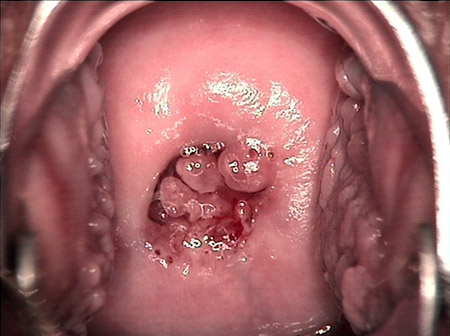

婦科leep手術(shù) 宮頸息肉

宮頸息肉

宮頸息肉 leep術(shù)后

宮頸息肉 leep術(shù)一周后

宮頸息肉 leep術(shù)兩周后

宮頸息肉 leep術(shù)三周后

宮頸息肉 leep術(shù)50天后